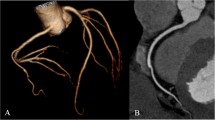

Based on the heart rate of 75 bpm identified in the ROC analysis, a patient-based analysis showed that 73 of 74 subjects (98.9%) in the PGT group and 78 of 80 subjects (97.5%) in the RGH group, respectively, had diagnostic image quality. Thus there is no statistically significant difference between the groups based on this heart rate threshold (P = 1.0). At heart rates >75 bpm,14 of 26 subjects (53.9%) in the PGT group and 17 of 20 subjects (85%) in the RGH group, respectively, had diagnostic image quality. There is statistically significant difference between two groups (P = 0.03) above the heart rate threshold. Figures 2 and 3 are representative examples of cases scanned with PGT, with average heart rates of 54 bpm and 92 bpm respectively, both ranked 4. Figure 4 is a clinical example showing the real-time arrhythmia handling capabilities of the PGT mode where the scan was paused (and x-rays turned off) during an arrhythmic event and resumed once sinus rhythm was restored—the image quality was not affected by the premature beat and the coronary image quality was ranked 4.

PGT-CCTA of a 55 year old female (BMI: 25 and mean HR: 56 ± 1.0 bpm) with an anomalous origin of the right coronary artery (RCA). a Curved multi-planar reformation (CMPR) of the right coronary artery (RCA) artery. b Volume rendered depiction showing coronary artery system with the anomalous origin of the RCA. The scan was centered at 75% physiologic cardiac phase. All segments were ranked 4 (excellent). Effective dose: 2.3 mSv